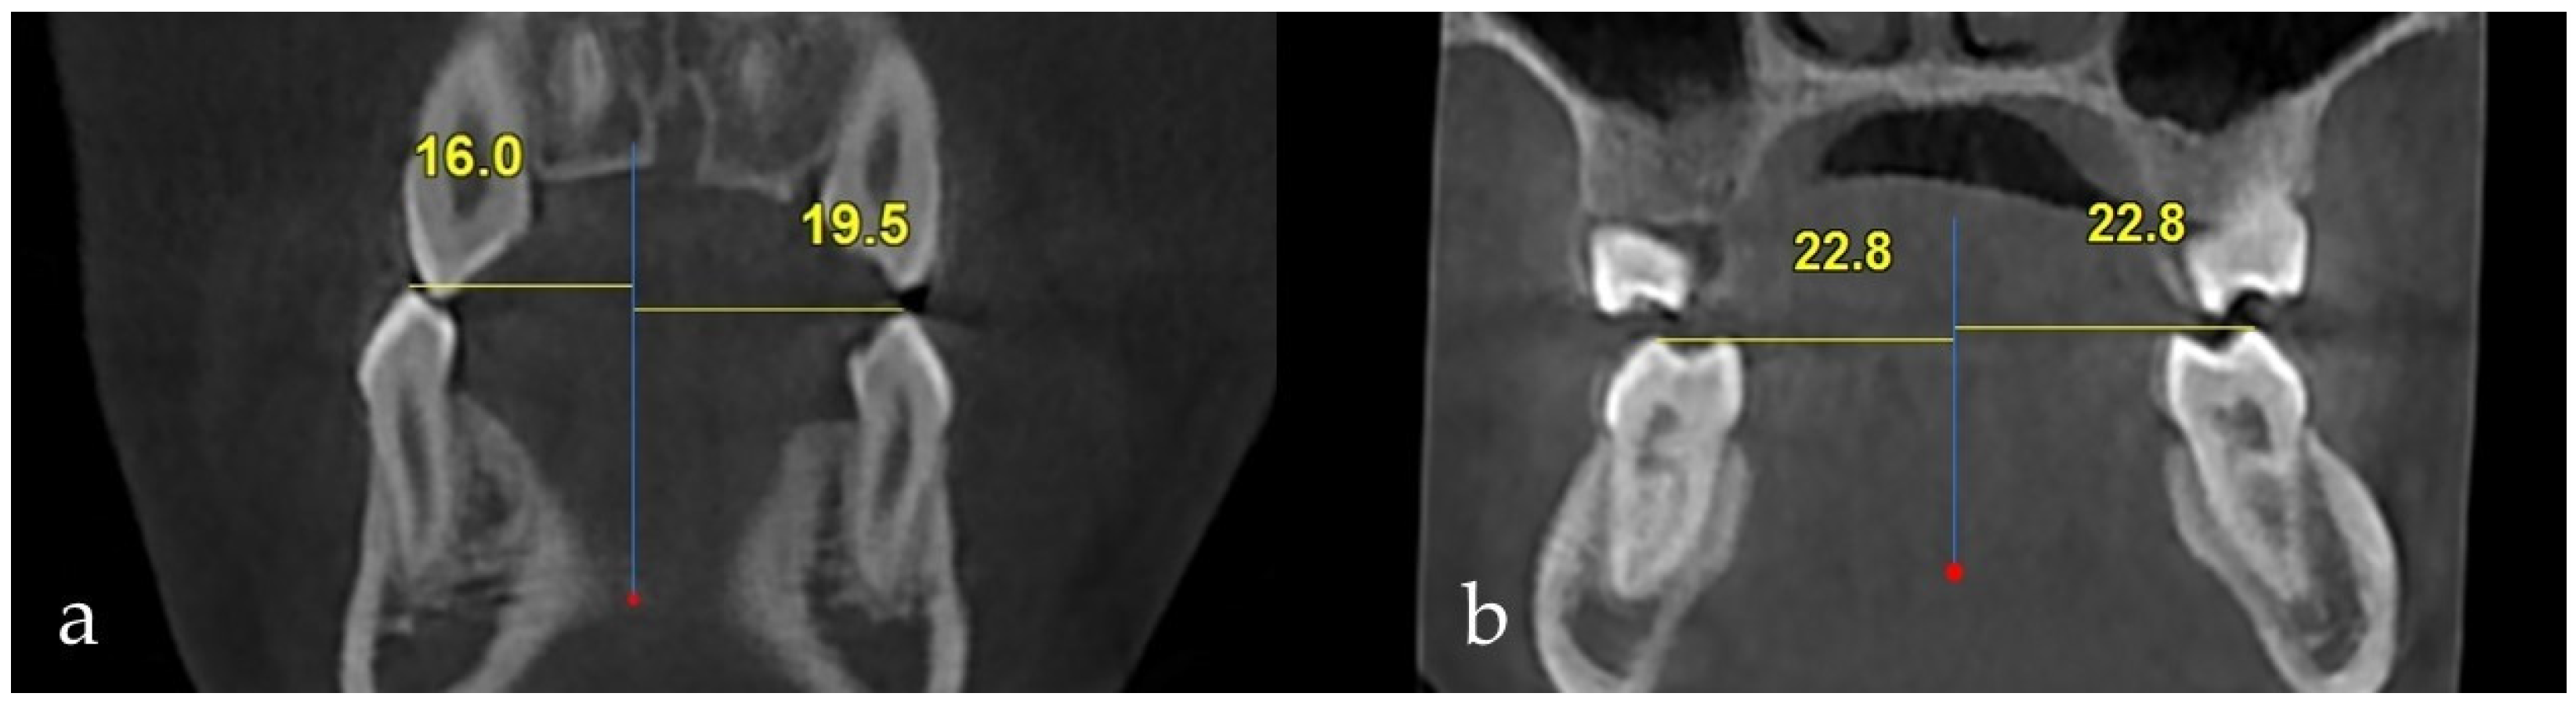

| Impacted Side | Non-Impacted Side | Test Statistic | ||

| Mean ± SD Median (IQR) | Mean ± SD Median (IQR) | z; t | p | |

| Interpremolar width | 15.69 ± 2.29 | 16.45 ± 1.42 | z = 1.864 | 0.062 |

| 16.00 (2.78) | 16.80 (1.65) | |||

| Intermolar width | 21.86 ± 2.27 | 22.44 ± 2.06 | t = 1.393 | 0.166 |

| 22.15 (2.90) | 22.35 (2.80) | |||